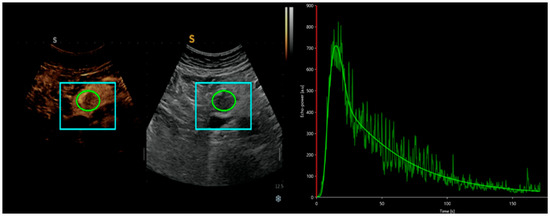

3.1. CEUS in the Differential Diagnosis of pNETs and Other Pancreatic Lesions

- Del Prete, M.; Di Sarno, A. ENETS Centre of Excellence Multidisciplinary Group for Neuroendocrine Tumors in Naples (Italy). Role of contrast-enhanced ultrasound to define prognosis and predict response to biotherapy in pancreatic neuroendocrine tumors. J. Endocrinol. Investig. 2017, 40, 1373–1380. [Google Scholar] [CrossRef]

- Yang, D.H.; Cheng, J. Prediction of Pathological Grades of Pancreatic Neuroendocrine Tumors Based on Dynamic Contrast-Enhanced Ultrasound Quantitative Analysis. Diagnostics 2023, 13, 238. [Google Scholar] [CrossRef]